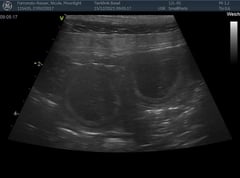

Nachdem die Geburt nicht voranschritt, entschlossen wir uns am Freitagabend 21.1.22 in die Klinik zu fahren. Nach einem Ultraschall war klar, es gibt einen Kaiserschnitt, der Uterus war gerissen und ein Welpli befand sich schon im Bauchraum. Alle Welpli waren fit mit tollen Geburtsgewichten zwischen 420 und 500g. Nachts um 2 Uhr fuhren wir nach Hause, die Welpli tranken schön bei Moon und alles sah gut aus. Aber Moon ging es am Morgen zusehends schlechter, sie bekam Fieber und war apathisch. Wieder in die Klinik, sie wurde stabilisiert und später wegen hohem Blutverlust nochmals operiert. Ein grosses Dankeschön der Tierklinik Basel, die uns übers Wochenende rund um die Uhr perfekt betreut haben und danke Melanie und Kuba fürs Blut spenden!